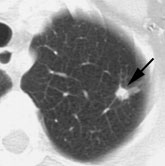

PET Imaging in Bronchogenic Carcinoma

PET imaging can have a significant impact on patient management by heightening suspicion for pulmonary malignancy, identifying unsuspected sites of disease, and by guiding selection of a biopsy site. Similarly, a negative PET scan indicates a low likelihood for malignancy and supports the use of conservative management and follow-up.